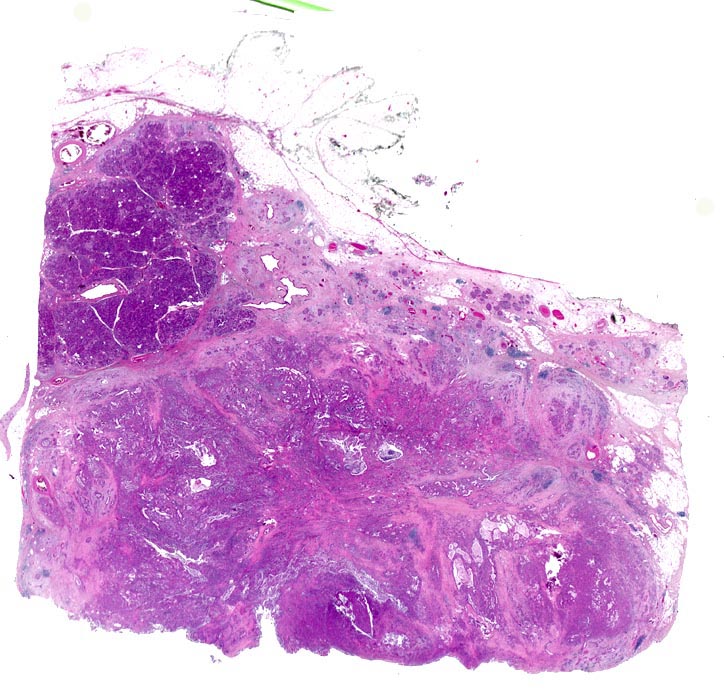

AP/ Duktales Adenokarzinom des Pankreas

Duktales Adenokarzinom des Pankreas

Die meisten Pankreaskarzinome sind mässig bis hoch differenziert und führen zu einer deutlichen desmoplastischen Stromareaktion (derbe Konsistenz). Hochdifferenzierte Tumoren (> 1502) können sehr ähnlich aussehen wie eine chronische Pankreatitis (> 4243). Im Gegensatz zur Pankreatitis sind die neoplastischen Drüsen verformt oder rupturiert und zeigen zelluläre Atypien (grosse polymorphe Kerne mit prominenten Nucleolen). Die Tumordrüsen sind unregelmässig im Stroma angeordnet und nicht lobulär wie in der Pankreatitis. Nicht selten ist eine Nervenscheideninvasion nachweisbar (> 5884). Gelegentlich zeigen die Gänge im tumorfreien Parenchym dysplastische Veränderungen oder der Tumor breitet sich intraduktal entlang des Pankreasganges aus.

• Unregelmässige Anordnung der Drüsen (keine Läppchenarchitektur erkennbar).

• Kribriforme Drüsenformationen.

• Inkomplette Drüsen mit unvollständigen Lumina und Infiltration des Stromas durch Tumoreinzelzellen.

• Nekrotische Tumorzellen in den Drüsenlumina.

• Ausgeprägte Polymorphie und Hyperchromasie der Tumorzellkerne.

• Desmoplastisches Stroma.

• Rechts oben Reste von nicht neoplastischem Pankreasparenchym mit fokaler chronisch obstruktiver Pankreatitis als Folge von tumorbedingten Gangobstruktionen: Vollständige Atrophie des exokrinen Pankreas bei erhaltenen Inseln. Ersatz des atrophen Parenchyms durch Fibrose. Chronisches Entzündungsinfiltrat.